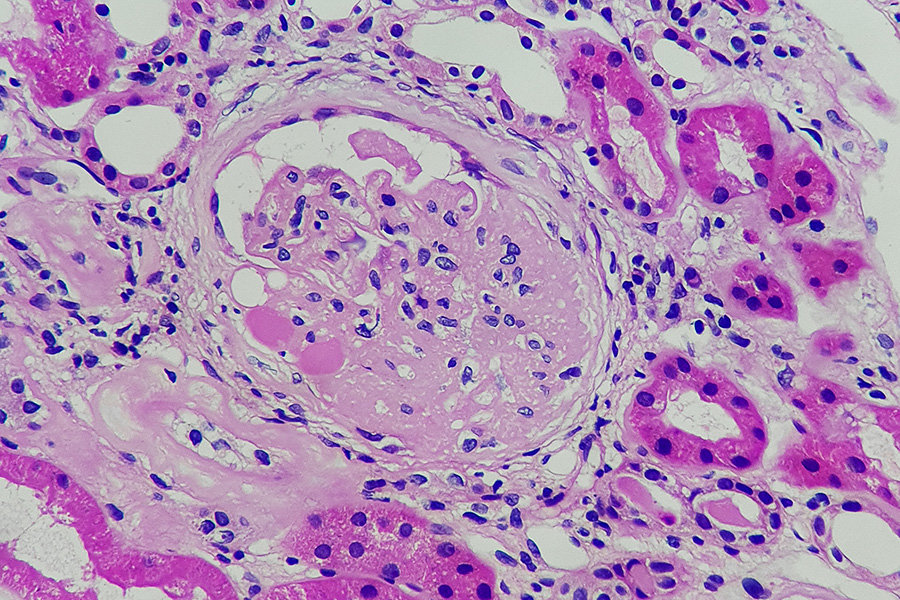

A diagnosis of Focal Segmental Glomerulosclerosis (FSGS) is a serious one. This condition, characterized by scarring in the kidney’s filters (glomeruli), is a leading cause of nephrotic syndrome and often leads to End-Stage Renal Disease (ESRD). Because FSGS is not a single disease but a pattern of injury, managing it effectively means digging deep to find the root cause.

Understanding the FSGS causes is the first step toward effective treatment. The injury that leads to scarring of the podocytes (the specialized filtering cells) can stem from genetic predisposition, underlying systemic diseases, or an unknown immune factor. This knowledge helps categorize the disease and determine the most appropriate therapy.